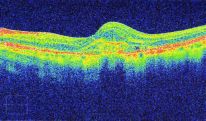

A 3D section of the layers ofthe retina and vitreous jellyA 3D section of the layers of the retina and vitreous jellyAge-related Macular Degeneration Dry FormAge-related Macular Degeneration Dry FormAge-related Macular Degeneration Wet FormAge-related Macular Degeneration Wet FormThe vitreous (jelly) pulling on the retinaThe vitreous (jelly) pulling on the retinaImage of Retina (back of the eye)Image of Retina (back of the eye)